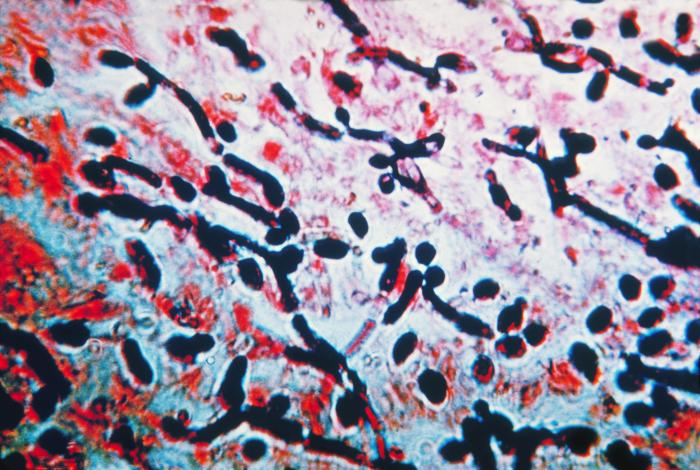

The investigation, where scientists analysed swabs from several everyday objects, revealed there were thousands of bacteria on the ubiquitous payment machines.

E.coli, which causes vomiting, was present on nearly all the surfaces, while poo and microbes that lead to urinary tract infections (UTIs) were found on self-service screens.

A bug commonly found in the vagina, mouth, throat and gut called Candida albicans, which can cause yeast infections, was also discovered on an escalator handrail.